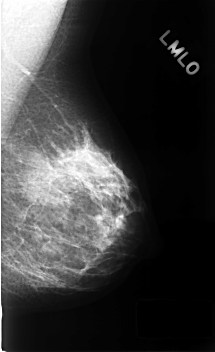

C_0330_1.LEFT_MLO

LEFT_MLO LINES 4568 PIXELS_PER_LINE 2784 BITS_PER_PIXEL 12 RESOLUTION 50 NON_OVERLAY